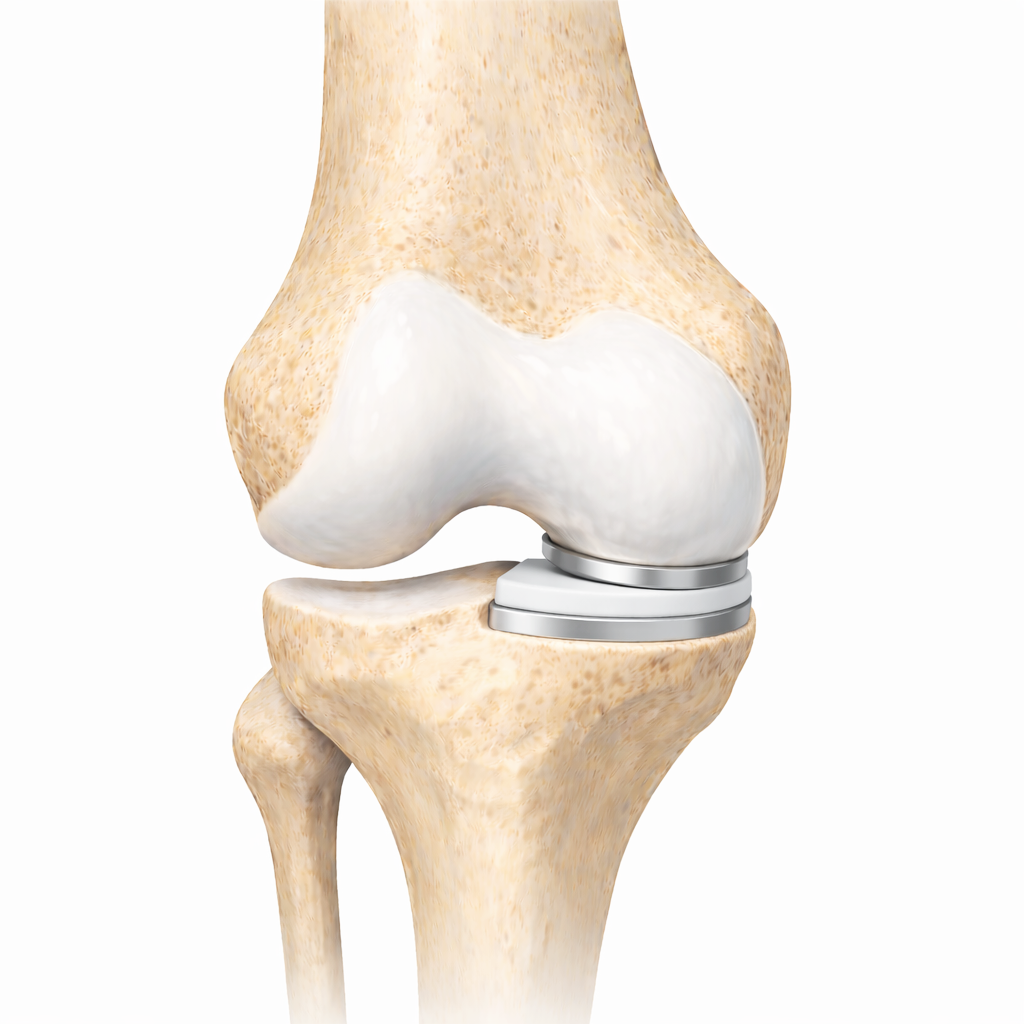

Medical illustration showing a partial knee replacement.

A partial knee replacement (unicompartmental knee arthroplasty) treats arthritis that affects only one part of the knee joint. Instead of replacing the entire knee, only the damaged compartment is resurfaced.

The knee has three compartments:

• Medial (inside)

• Lateral (outside)

• Patellofemoral (behind the kneecap)

When arthritis is isolated to one of these areas, a partial knee replacement can relieve pain while preserving the remaining healthy cartilage, bone, and ligaments.

Because much of the natural knee is maintained, many patients report a knee that feels more natural compared with a total knee replacement.